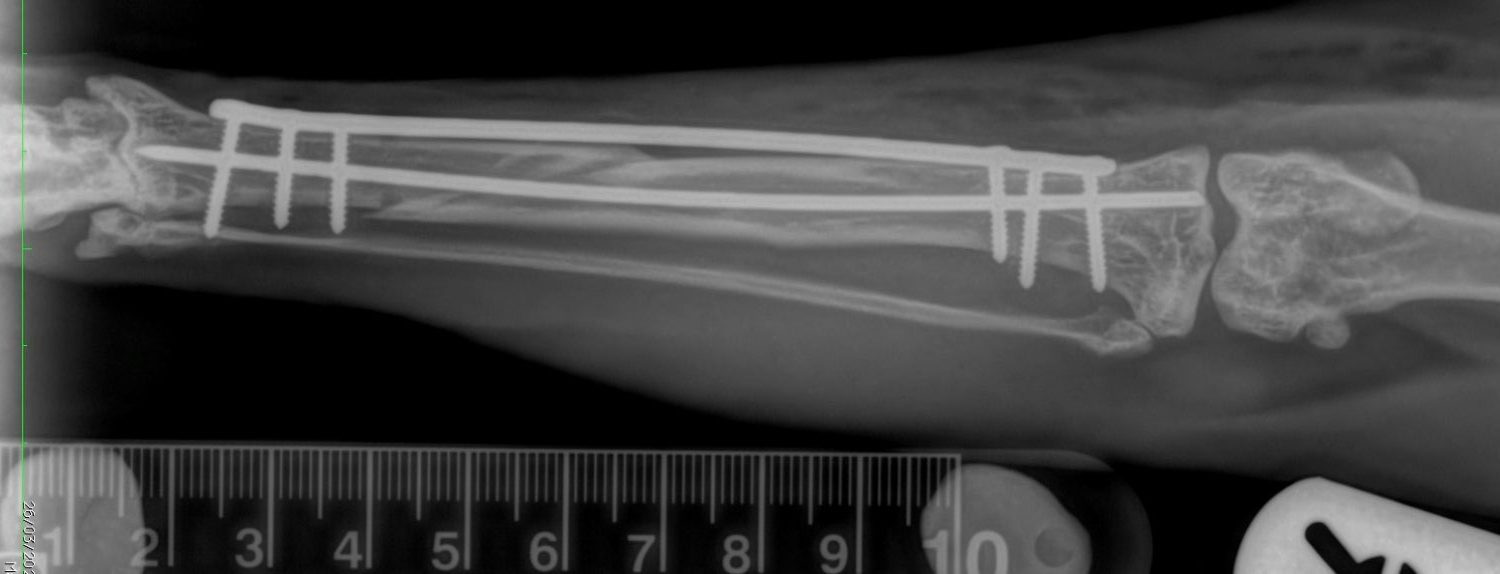

On the day of surgery Tilly was anaesthetised and an epidural was administered. Surgery was performed by Martin and Penny at our Meopham Hospital. A pin was surgically placed into the centre of the bone fragments along with a plate on the boney shaft. Post-operative radiographs revealed good alignment so Tilly was woken up and transferred to our nursing care for recovery.

Before and after radiographs can be found within the carousel below along with intra-operative photographs.